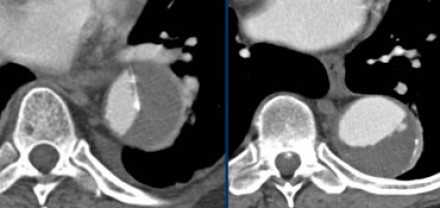

![13]()

![14]()

- Симптом паутинок — соединительные останки медии, который визуализируется в ложном просвете, который также часто тромбируется.

- Если один просвет, окружен другим, то этот просвет является истинным, что всегда встречается при диссекциях типа А.

- На нижележащих изображениях представления диссекция типа А. Истинный просвет окружен ложным, также визуализируется симптома клюва, что объясняется постоянным систолическим давлением.